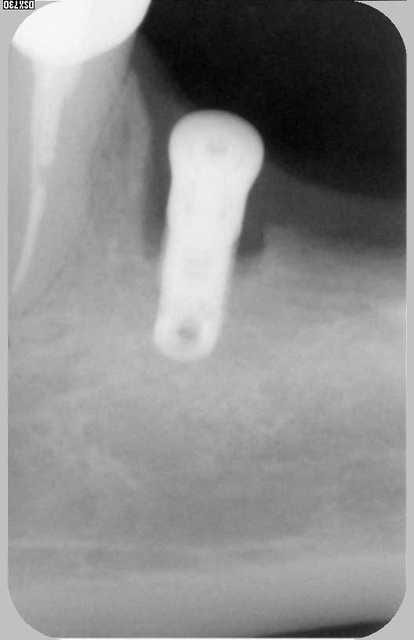

Je revois la patiente aujourd'hui et voila la radio: l'image suspecte a disparu presque complètement, implant complètement silencieux et fixe... todo isso e muito bem!!!

Y'a quand même un tissus fibreux non osseux, mais l'implant a suffisament d'os ailleurs autour de lui pour tenir le coup quand même.

P'être bien que ça ne bougera jamais, mais une RX tout les ans me semble assez raisonnable, juste au cas où...

oui Chicot mais s'agit il de fibres ou d'os moins dense ? les limites ne sont plus nettes comme au début.

ben au bout de 2 ans je dirais.......fibrose !